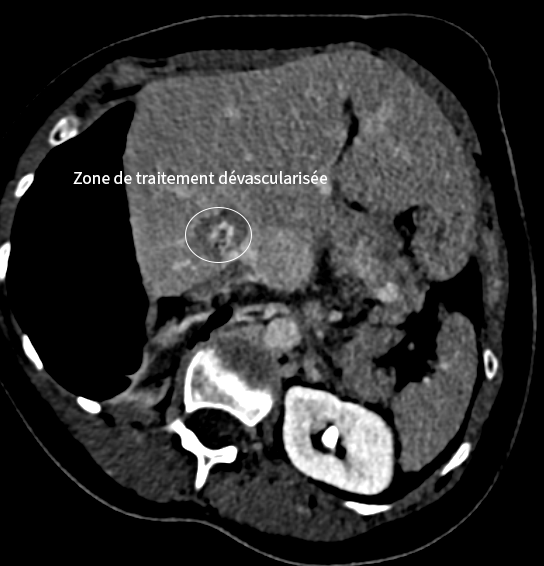

Traitement hépatique par micro-ondes

Dans un second temps, la métastase hépatique est traitée par thermoablation micro-ondes, avec protection des organes voisins grâce à une technique d’hydrodissection.

Résultat

Le contrôle à distance montre une réponse complète des lésions, sans nouvelle métastase, permettant la poursuite d’une simple surveillance.

Images du traitement des organes (poumon et foie) avant, pendant et après le traitement.